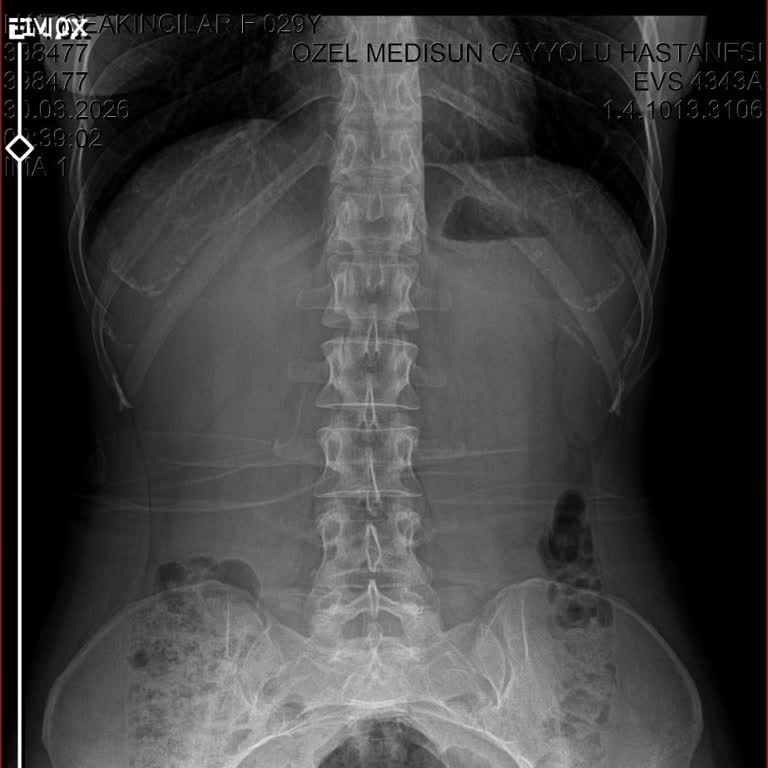

30.03.2026 tarihinde yaşadığım bir düşme sonrası Ankara’daki Medisun Hastanesi’ne başvurdum. Muayene sırasında özellikle kuyruk sokumumun üzerine düştüğümü ve bu bölgede ciddi ağrı hissettiğimi açıkça ifade etmeme rağmen yalnızca bel bölgeme yönelik röntgen çekimi yapıldı. Yapılan değerlendirme sonu...